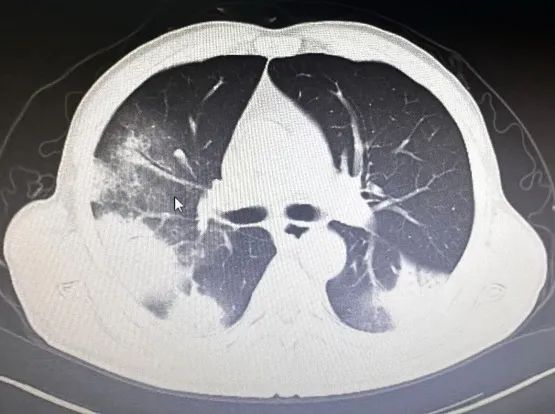

经积极抗感染治疗,患者仍持续处于稽留热,体温最高达39.8℃,并逐渐出现胸闷、气短症状伴有咳嗽、咳痰。右肺中下叶可闻及少量散在湿啰音及胸膜摩擦音。感染指标持续上升,复查肺部CT提示:双肺多发感染性病变,较前进展。

调整治疗后,患者病情仍未见好转并逐步恶化,遂转入ICU继续治疗。在我院ICU予以无创呼吸机通气,为了明确病因,行支气管镜检查取样成功,结果显示:鹦鹉热衣原体。结合血常规、CRP和胸部CT检查以及他饲养鸟类动物病史,此时就明确了,原来患者这次是鹦鹉热衣原体引起的肺部感染——俗称“鹦鹉热”。

重症鹦鹉热患者可于短期内出现呼吸衰竭和ARDS等呼吸系统症状。胸部CT检查以炎性病变始于单侧肺下叶多见,加重后累及双侧肺叶,上下肺均可受累,可合并有小片状的磨玻璃影、结节影、实变影和小叶间隔增厚,以胸膜下分布为主,常见“支气管充气征”、“细网格征”,可见“晕征”,常伴有胸腔积液,可伴有肺门及纵隔淋巴结肿大。治疗上常用的Cps抗菌药物包括四环素类、新型四环素类衍生物、大环内酯类和氟喹诺酮类等药物。